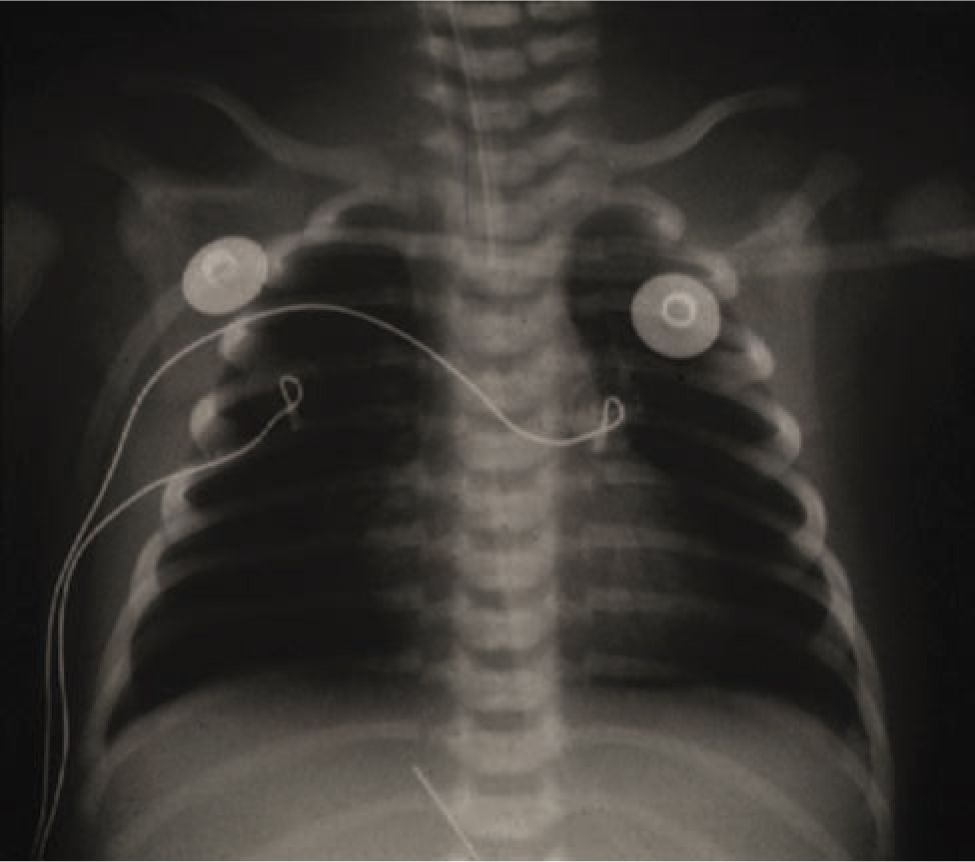

a) Sizeable oligemic area in right lung. The embolus in right pulmonary

a) Sizeable oligemic area in right lung. The embolus in right pulmonary What Is Oligemic Lung Fields It is one of several described signs of pulmonary. Westermark sign is a sign of pulmonary embolus seen on chest radiographs. Radiographic findings in acute pulmonary embolism (pe) are uncommon. Each of these zones occupies approximately one third of the height of the lungs. For the purpose of description the lungs are divided into zones: Whatever the mechanisms, the end. What Is Oligemic Lung Fields.